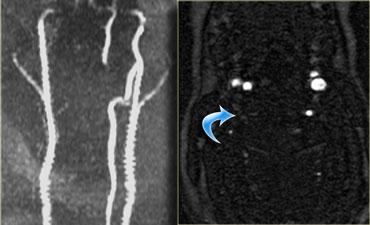

Đầu tiên chúng tôi trình bày hình CT mặt phẳng coronal và axial với cửa sổ mô mềm.

Có vật liệu tăng tỷ trọng ở phía sau khoang đĩa đệm, rất gợi ý thoát vị đĩa đệm do chấn thương.

Tụ máu ngoài màng cứng cần được đưa vào chẩn đoán phân biệt, nhưng dấu hiệu này chỉ giới hạn ở vùng khoang đĩa đệm, khác với hình ảnh của khối máu tụ.

Tiếp tục với hình MRI.